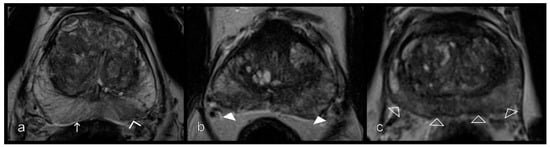

Figure 4.

Different levels of enhancement on contrast-enhanced csVIBE sequences in the peripheral zone. (a) No, (b) mild (white arrows), and (c) severe and early enhancement (arrowheads). No and mild enhancement were combined. csVIBE, native T1 and prototypical dynamic T1 gradient echo sequence.